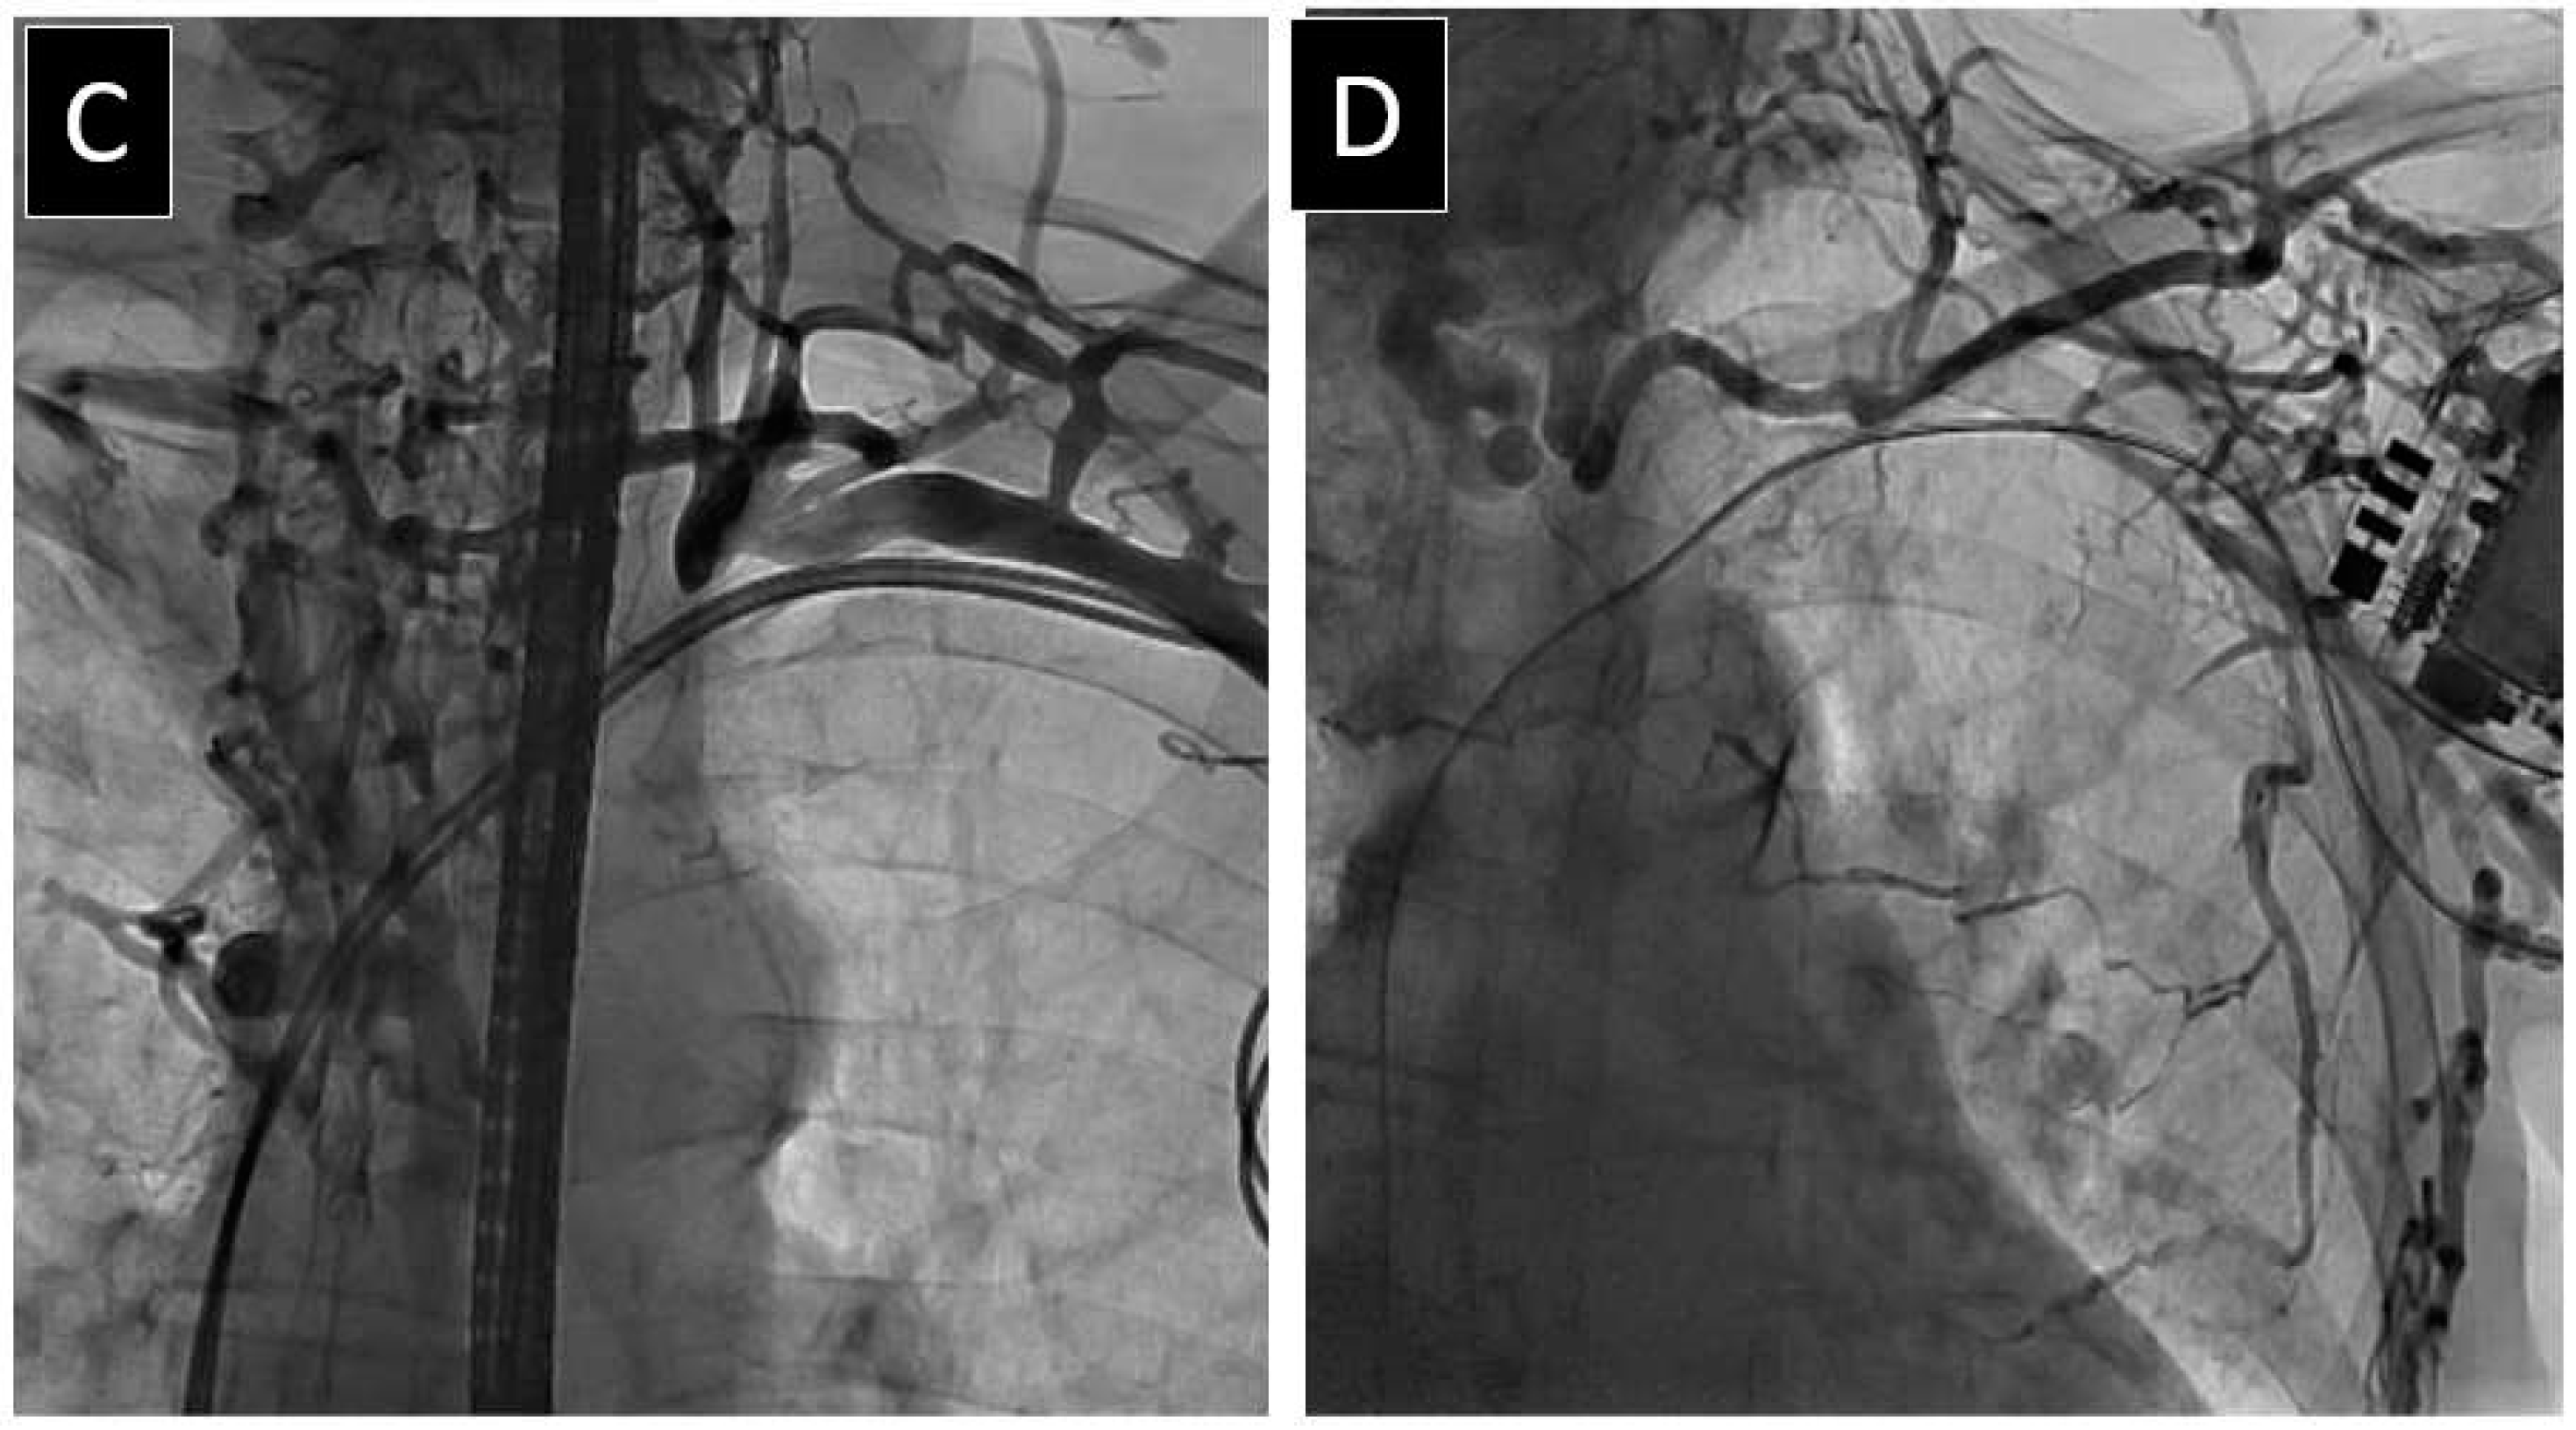

2.2. Venography Procedure

2.3. Lead Extraction Procedure